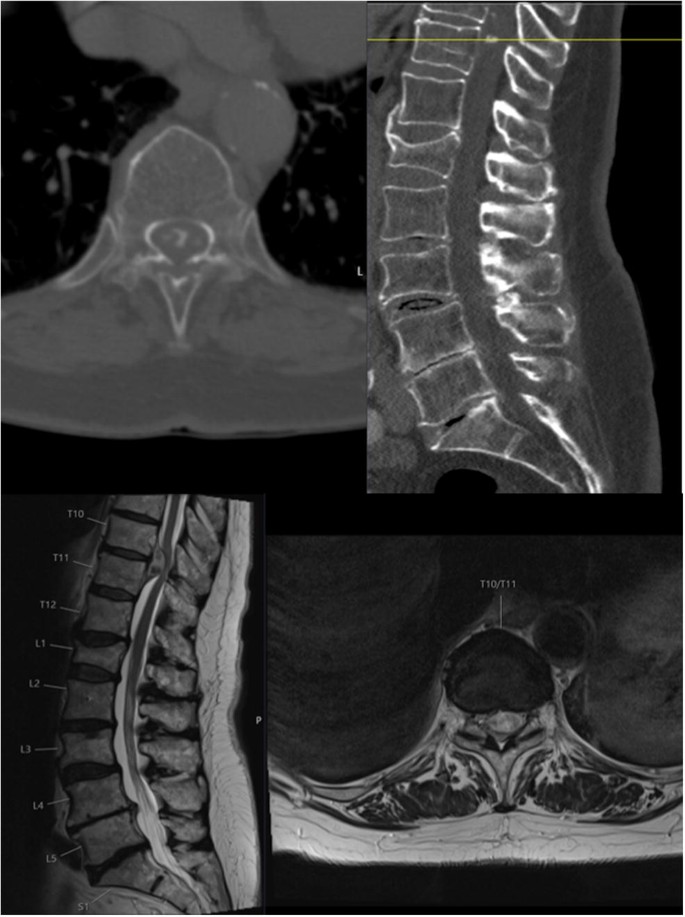

T11-t12 disc bulge symptoms-At T1112 there is a moderate posterior disc herniation which begins in the left paracentral position, but extruded disc material is seen extending caudally behind the T12 vertebra and Magnetic resonance imaging study showed a bulging disc and posterior osteophytes at T11T12 Results Surgical removal of the herniated disc and osteophytes rapidly

If the discs become displaced, or herniated, they can impinge on surrounding structures and cause uncomfortable symptoms The most commonly involved discs are the ones located between the Three of four patients with T11–T12 disc herniation experienced lower extremity weakness, and three patients had accentuated patellar tendon reflex Sensory disturbance was lt;p>You may not have any symptoms as probably most people who have disc bulges are completely asymptomatic But if you do, you may notice cirmuferential pain or